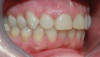

After several years and many consultations, the patient finally agreed to move forward with the recommended treatment. The patient's pretreatment condition is depicted in Figure 1 through Figure 3. Upon evaluation, several conditions were documented. The observation of a more coronally positioned gingival margin on the maxillary anterior teeth was noted. The differential diagnosis of dentoalvealor extrusion versus altered passive eruption was considered. The process of altered passive eruption was ruled out after appropriate bone sounding and palpation of the cemento-enamel junction (CEJ) apical to tooth Nos. 7 through 10. The gingival margin and bone heights were determined to be localized in a normal position within the gingival sulcus. This confirmed the diagnosis of dentoalveloar extrusion.10 As the linguals of the upper teeth were destroyed with acidic exposure, the teeth continued to erupt into function. Observations also included buccal collapse of the arches, malalignment of teeth, incisal wear, and dentoalveolar extrusion of the lower anterior teeth. A thorough smile design work-up was completed using numerous intraoral and extraoral radiographs and photographs. The lower incisal edges, particularly of tooth Nos. 24 and 25 showed signs of extrusion and wear but since the incisal edges closely followed the curvature of the lower lip line and the patient was only interested in maxillary treatment, their intrusion was limited to leveling and aligning the incisal edges. The preferred treatment option in this type of case is to consider orthodontic intrusion of maxillary teeth to relevel the gingival margins and subsequently increase occlusal clearance between arches for restorations. At that point, a treatment plan was developed that would address incisal edge position, which had shortened over time, and the appearance of gingiva versus tooth structure during a full smile.11 In addition, the photographs were used to evaluate the curvature of her smile, the midline of the teeth to the face, and the overall esthetics of the smile.

Fig 1. Maximum intercuspation showing worn incisal edges and altered gingival curvature of the maxillary arch at patient’s initial presentation.

Figure 1